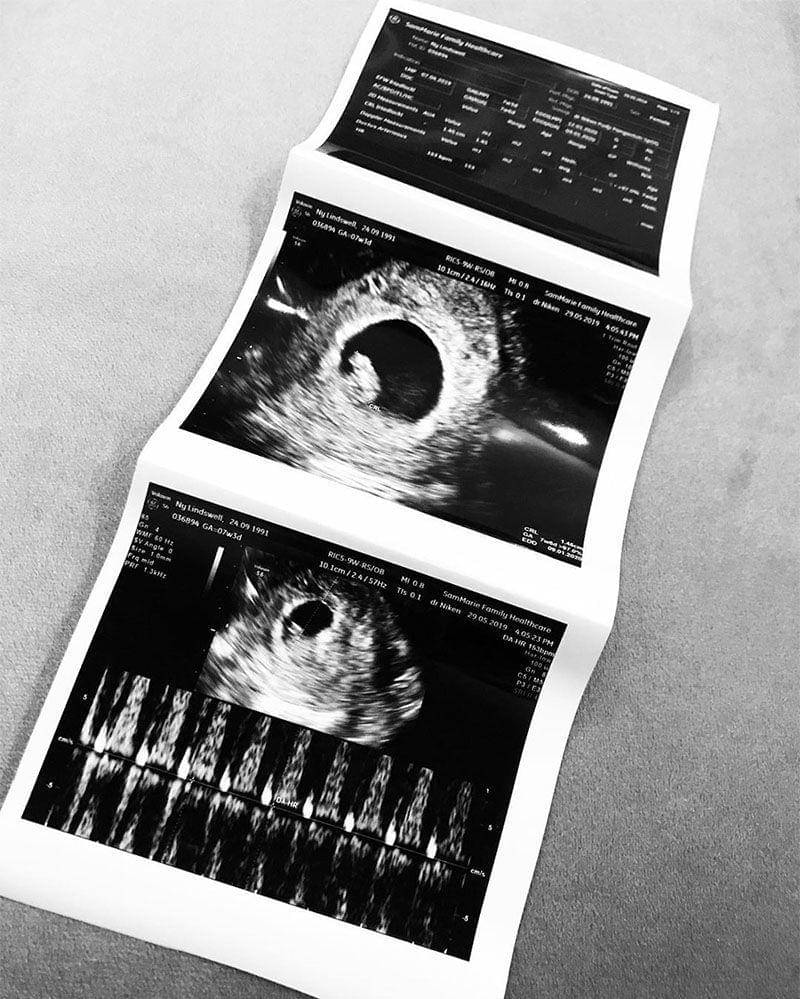

Unggah Foto Hasil USG, Lindswell Umumkan Hamil Anak Pertama

Nama Lindswell Kwok tentu sudah tidak lagi asing untuk didengar ya, Ma. Ratu Wushu tanah air yang sudah menikah dengan Achmad Hulaefi pada Minggu (9/12/2018) lalu ini, baru saja mengunggah foto hasil USG di Instagram pribadinya.

Lindswell dan sang Suami kompak menggunggah hasil USG dari anak pertamanya.

"Alhamdulillah segala puji bagi Allah," tulis Achmad Hulaefi ketika mengunggah foto tersebut.

Jika diperhatikan hasil USG yang diunggah pasangan ini memperlihatkan usia kehamilan Lindswell sudah masuk minggu ke-7 di trimester pertama.

Melalui unggahan fotonya di Instagram, hasil USG dari Lindswell mengatakan bahwa usia kandungannya sudah memasuki minggu ke-7. Perlu diketahui bahwa perkembangan janin pada minggu ke-7 sudah mirip ukurannya dengan biji buah apel hijau dengan panjang 1,27 cm.